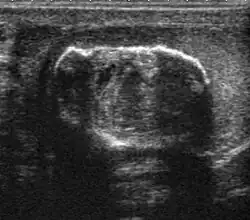

Patients with testicular lymphoma are usually old aged around 60 years of age, present with painless testicular enlargement and less commonly with other systemic symptoms such as weight loss, anorexia, fever and weakness. Bilateral testicle involvements are common and occur in 8.5% to 18% of cases. At sonography, most lymphomas are homogeneous and diffusely replace the testis [Fig. 7]. However focal hypoechoic lesions can occur, hemorrhage and necrosis are rare. At times, the sonographic appearance of lymphoma is indistinguishable from that of the germ cell tumors [Fig. 8], then the patient's age at presentation, symptoms, and medical history, as well as multiplicity and bilaterality of the lesions, are all important factors in making the appropriate diagnosis.

At ultrasound, the findings of acute epididymitis include an enlarged hypoechoic or hyperechoic (presumably secondary to hemorrhage) epididymis [Fig. 20a]. Other signs of inflammation such as increased vascularity, reactive hydrocele, pyocele and scrotal wall thickening may also be present. Testicular involvement is confirmed by the presence of testicular enlargement and an inhomogeneous echotexture. Hypervascularity on color Doppler images [Fig. 20b] is a well-established diagnostic criterion and may be the only imaging finding of epididymo-orchitis in some men.